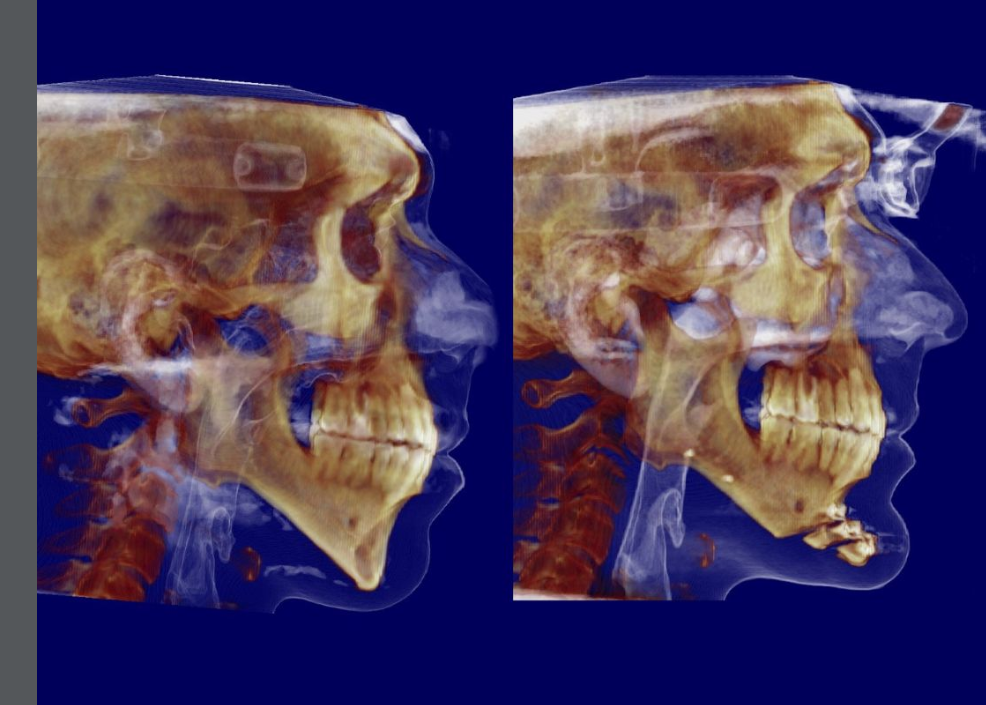

They cut the chin 2 times. Usually I see a chin getting cut only 1 time.

Surgeon: Dott. Valerio Ramieri

No bone graft was done look at the after it's just held by platesStair step genio with bone grafts, because the total advancement was 16 mm which is impossible with the traditional osteotomy. It also caused a step off in the soft tissue.

The patient needed jaw surgery but presumably he declined it for some reason but still wanted an improvement.